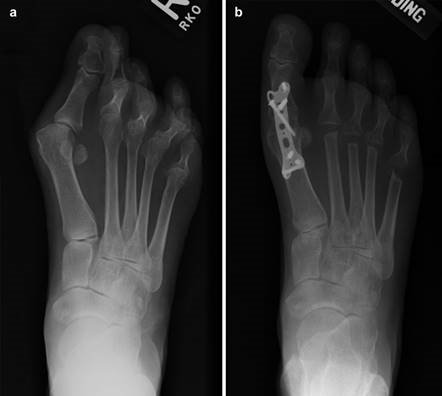

Weight-bearing anteroposterior (AP), lateral, and sesamoid axial radiographs are mandatory. On the AP view, the surgeon measures the Hallux Valgus Angle (HVA, normal < 15°), the Intermetatarsal Angle (IMA, normal < 9°), and the Distal Metatarsal Articular Angle (DMAA). The lateral view is scrutinized for Meary's angle (talo-first metatarsal angle) to identify midfoot collapse, as well as the presence of dorsal osteophytes indicative of hallux rigidus. The sesamoid axial view is critical for assessing the degree of sesamoid subluxation and the integrity of the crista.

Image

To achieve multiplanar correction, the surgeon must address the sagittal, coronal, and transverse planes. The first metatarsal is plantarflexed to restore the longitudinal arch, rotated out of pronation to realign the sesamoids, and translated laterally to close the IMA. Subchondral drilling or feathering is performed to optimize the biological environment for fusion. Fixation is traditionally achieved with two or three crossed solid or cannulated screws (typically 3.5mm or 4.0mm). Recently, plantar or medial locking plates have gained immense popularity due to their superior biomechanical construct, allowing for earlier weight-bearing. Bone graft or orthobiologics may be packed into the arthrodesis site to stimulate osteogenesis.

Positioning of the fusion is the most critical step of the operation. The hallux must be positioned in 10-15 degrees of valgus, 15-20 degrees of dorsiflexion relative to the first metatarsal, and neutral rotation. Excessive dorsiflexion causes shoe impingement, while insufficient dorsiflexion leads to vaulting during gait and interphalangeal joint arthritis. Fixation is most reliably achieved using a pre-contoured dorsal locking plate combined with a lag screw crossing the fusion interface.